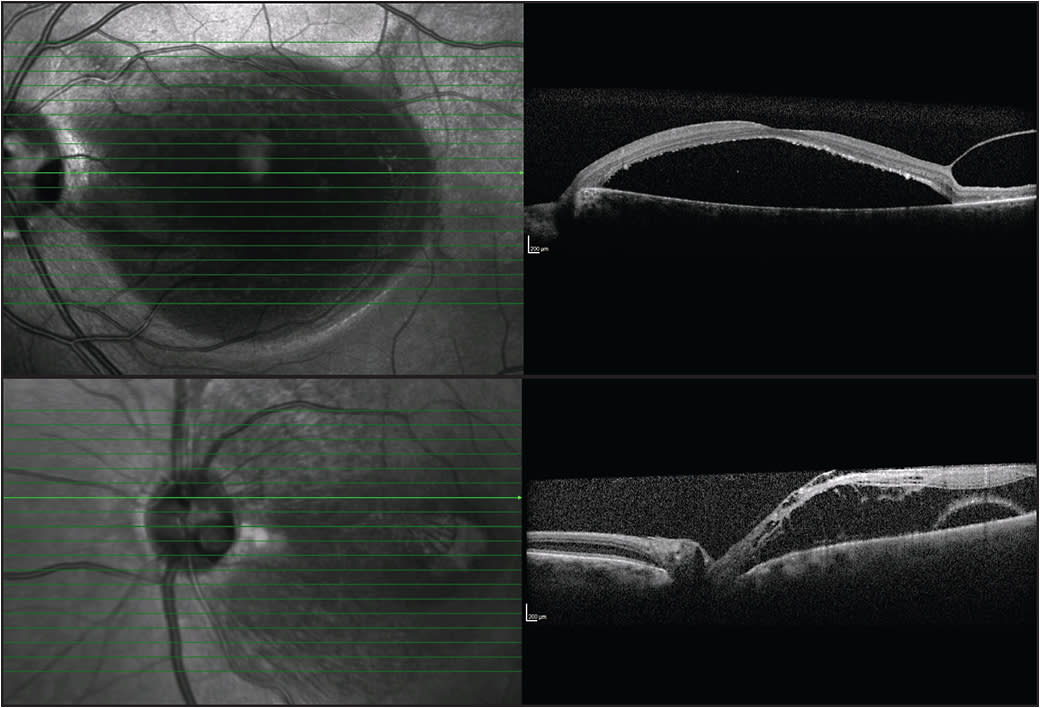

In isolation, ODPs are often asymptomatic; however, they may go on to develop an associated neurosensory detachment of the macula (Figure 1), with subsequent reduction in vision. This maculopathy occurs in 25% to 75% of patients with ODPs,3,4 and it usually occurs in the third to fourth decade of life.5

Figure 1. Images of a patient with optic disk pit maculopathy. The pit size may be from one-eighth to half the diameter of the optic disk. There is a neurosensory detachment of the fovea.

Figure 2. ODP maculopathy. Note the connection between the subretinal space and ODP on optical coherence tomography.

Figure 3. ODP maculopathy is a neurosensory detachment that can often be associated with a macular schisis. Top) Neurosensory detachment only. Bottom) Combined neurosensory detachment with a schisis.